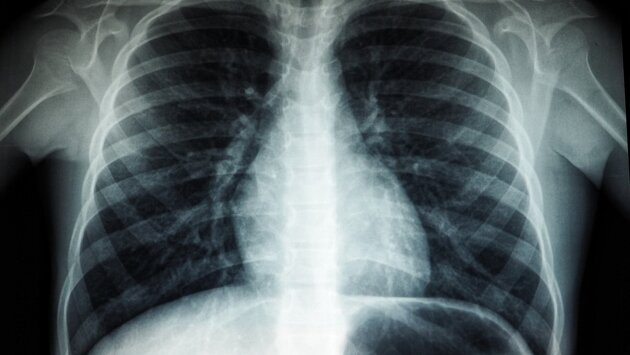

За три первых месяца 2023 года у 2,5 тысячи жителей Удмуртии выявили болезни органов дыхания

Ижевск. Удмуртия. В Удмуртии за первые три месяца 2023 года выявлено 2,5 тыс. случаев болезней органов дыхания. Об этом сообщает пресс-служба Минздрава Удмуртии.

Данный вид заболеваний является одним из наиболее часто выявляемых. По итогам прошлого года на диспансерном наблюдении состоят более 47 тыс. пациентов.

«Новая коронавирусная инфекция очень повлияла на развитие болезней органов дыхания. Если вспомнить первые волны болезни, то в большинстве случаев она довольно быстро переходила в пневмонию, поражение легких у пациентов было достаточно серьезным. Поэтому сейчас мы наблюдаем последствия перенесенного ковида», – рассказала главный внештатный пульмонолог Минздрава Удмуртии Оксана Стародубцева.

Медики советуют, что чем раньше начнётся лечение, тем меньше осложнений последует в будущем.